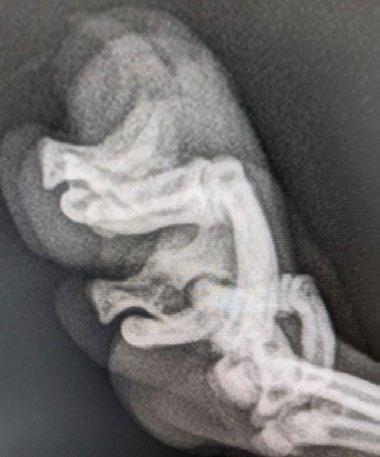

Next Steps: X-ray & Debulking Surgery

Roger then underwent chest and foot radiology on the 21 May. No bone lysis or involvement was present on the digital lesion. Chest radiography dorsoventral and lateral were within normal limits, with no evidence of metastatic lesions (i.e. NO lung digit syndrome). At this point, the lump was debulked with a scalpel under IV sedation and local anaesthesia as Roger is the bestest boy. The lump was approximately 0.6cm x 0.4cm in size, and ovoid; it was sent for histopathology. It had a caseous 1mm area in the centre of the lesion when dissected in half.

Figure 3 A B and C. Radiographs of the chest and distal limb